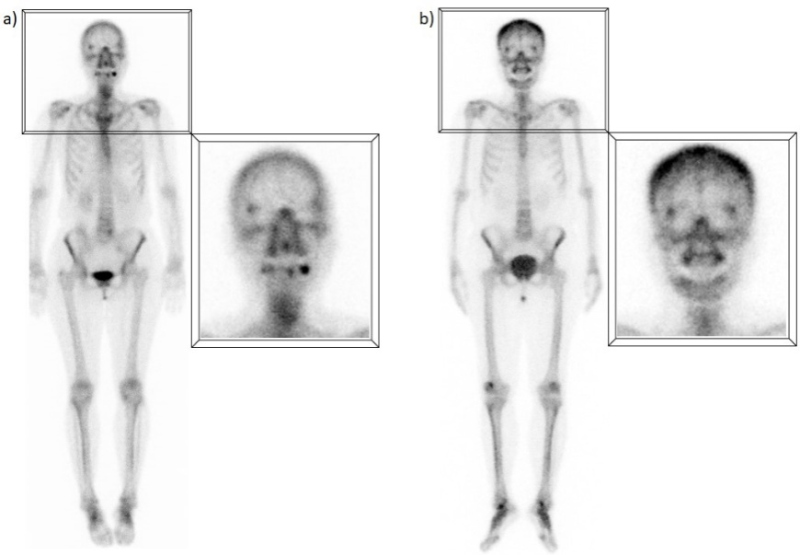

D) Captación del área sino-nasal

Es quizás uno de los hallazgos más frecuentes y su interpretación debe ser cuidadosa, dado que puede representar tanto una patología como una variante normal. A menudo, la captación en la región nasal y maxilar representa la remodelación ósea en las paredes de las cavidades paranasales debido a cambios inflamatorios crónicos(7); esto se ha observado no sólo en pacientes con sinusitis crónica, sino también con rinitis alérgica. Sin embargo, algunos estudios han encontrado que un porcentaje significativo de pacientes (hasta un 42%) sin síntomas respiratorios continúan presentando este patrón de captación, aunque de forma menos prominente(8). En muchos de estos pacientes se ha descrito una captación extra ósea, probablemente secundaria a un mayor flujo sanguíneo y permeabilidad capilar de los tejidos regionales, ya que la mucosa nasal es un área muy vascularizada(9) (fig. 4).

E) Captación esternal

Generalmente este hallazgo se atribuye a cambios degenerativos de las articulaciones esternoclaviculares, bastante frecuentes y que aumentan con la edad, ya que se trata de articulaciones sinoviales que soportan un estrés constante(10). Sin embargo, algunos estudios han descrito patrones de captación normales específicos en el esternón, relacionados con la edad, que no necesariamente representan cambios articulares. Los hallazgos sugieren que una captación difusa, homogénea y leve es normal en pacientes jóvenes, mientras que un patrón más heterogéneo y segmentario, con mayor actividad en los bordes óseos, también puede ser completamente normal en pacientes de edad avanzada(11). Asimismo, la captación focal a nivel de la articulación manubrio-esternal o ángulo de Louis es un hallazgo frecuente, independientemente de la edad, que en la mayoría de los casos puede explicarse por la osificación a nivel de la sínfisis o la presencia de crestas óseas (fig. 5).